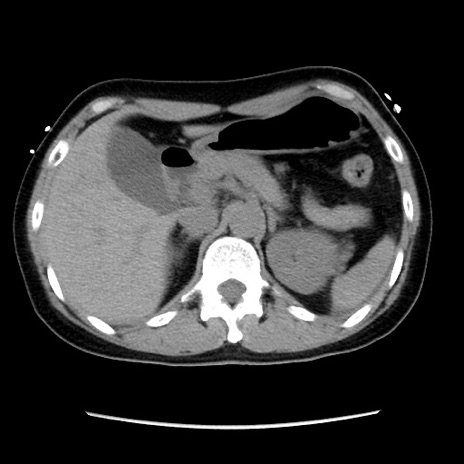

冠状断像

【症例】 50歳代女性

【主訴】 腹痛

【現病歴】前日生レバーを食べた。今朝に排便あり。 昼前に突然発症の腹痛を生じ、当院救急外来を受診した。

【既往歴】 子宮筋腫にてで子宮全摘後

【身体所見】 意識清明、腹部:平坦、軟、下腹部やや左を中心に圧痛・反跳痛あり、筋性防御あり

【データ】WBC 7800、CRP 0.07